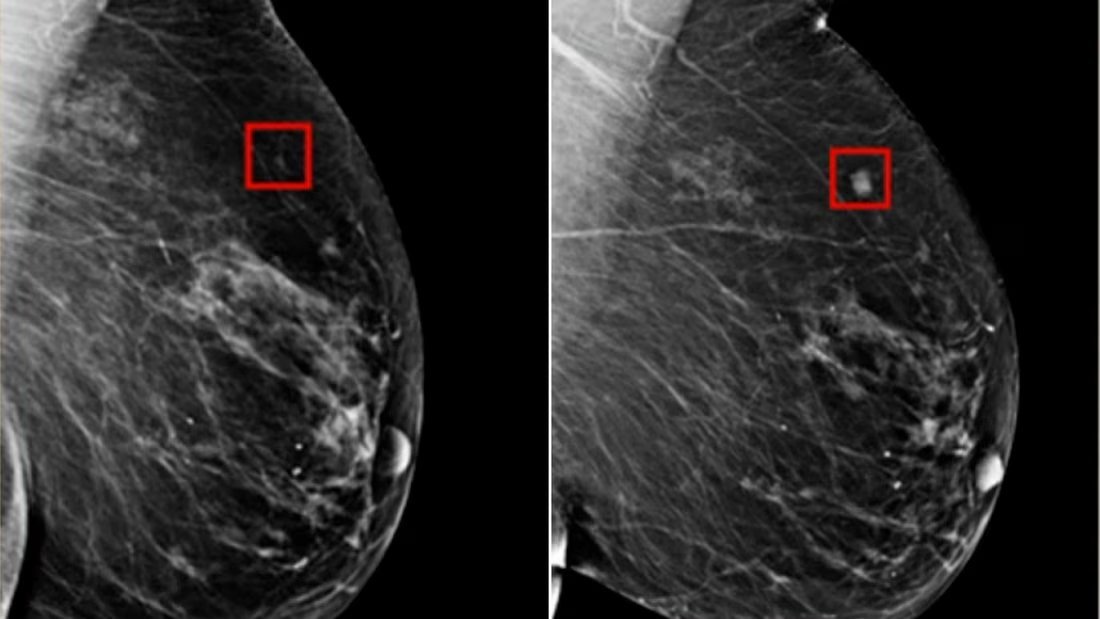

La vraie valeur de l'IA se trouve ici, dans la médecine👇 L'intelligence artificielle a détecté un cancer du sein 4 ans avant qu'il ne se développe. Source: edition.cnn.com/videos/health/…

L'intelligence artificielle a détecté un cancer du sein 4 ans avant qu'il ne se développe.